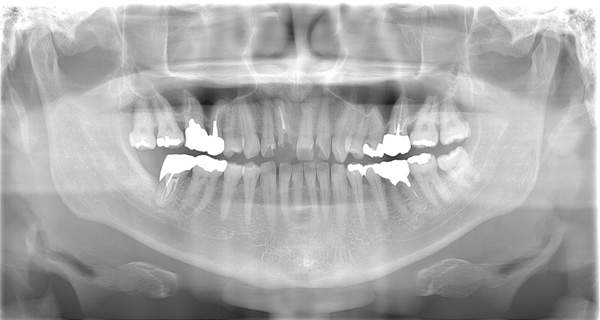

| 年代・性別 | 50代 女性 |

|---|---|

| 主訴 | 左上のブリッジがグラグラして外れそう |

| 治療期間 | 約18ヶ月 |

| 費用 | 1,600,000円 |

| 治療内容 | インプラント、骨造成、サイナスリフト、セラミック修復 |

| 治療に伴うリスク | インプラント周囲炎 セラミックの破折、脱離 |